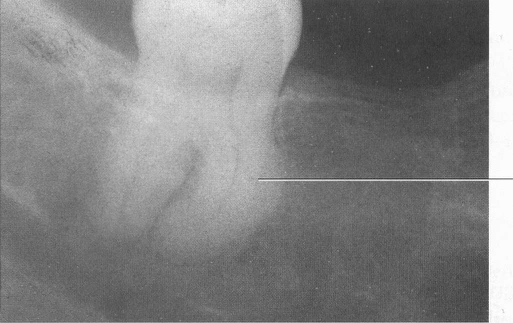

Hypercementosis

Excess cementum formation